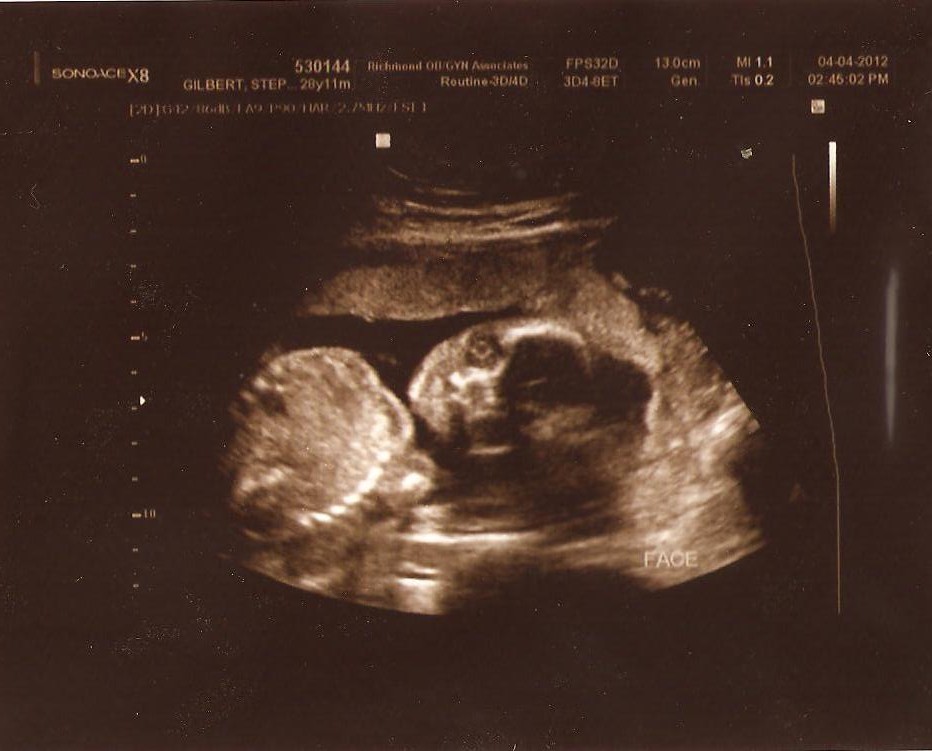

Here are baby girl's 20 week ultrasound pics from last week:

IT'S A GIRL!!!